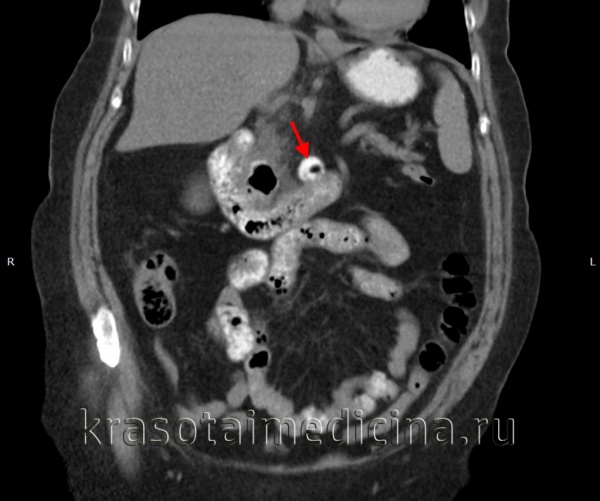

У меньшей части больных с дивертикулитом симптомы локального и системного воспаления останутся или уменьшатся через пару дней. Именно сейчас вы должны рассмотреть вероятность развития осложненных форм заболевания, в частности, назначить абдоминальную КТ, чтобы лучше разобраться с патологической анатомией. Амброзетти в Женеве разработал критерии определения степени тяжести острого дивертикулита по данным КТ, в соответствиии с их клинической значимостью:

• Легкий приступ — утолщение кишечной стенки более чем на 5 мм с признаками воспаления околокишечной жировой клетчатки.

• Тяжелый приступ — то же + абсцесс, наличие газа вне просвета кишки или вытекание контрастного препарата.

Около половины больных, у которых данные КТ расцениваются как «тяжелый приступ», требуют операции при госпитализации или вскоре после нее. Более существенно, что у другой половины больных не требуется операция на основе КТ-находок, оцениваемых в сравнении с клинической картиной.

КТ ОБП. Дивертикул горизонтальной части 12-перстной кишки, заполненный частично контрастом, частично – газом.